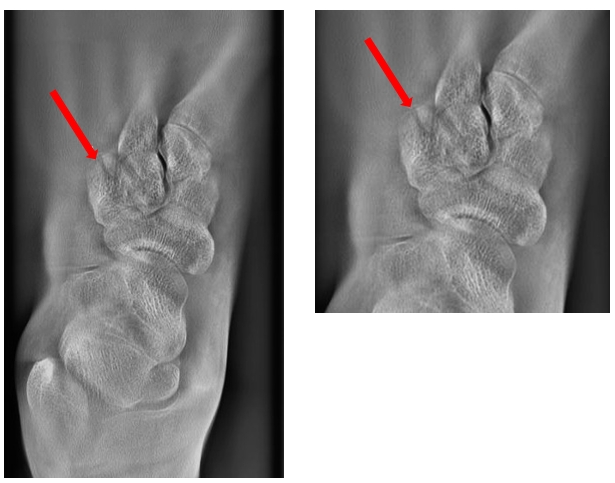

病例一:女,25歲。左足被電動(dòng)車砸傷。

通過斷層融合圖像分析,為楔骨骨折。